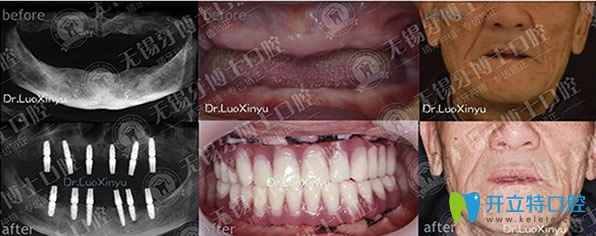

牙博士口腔種牙好不好,樸東信院長(zhǎng)全口種植牙代表案例:

牙博士口腔樸東信院長(zhǎng)全口種植牙代表案例

無(wú)錫牙博士口腔樸東信院長(zhǎng),種植牙技術(shù)適用于各種缺牙類型,美觀舒適,媲美真牙,咀嚼功能強(qiáng),種植牙后,想要具有和天然牙一樣的功效,長(zhǎng)期使用,需要保持良好的口腔衛(wèi)生。